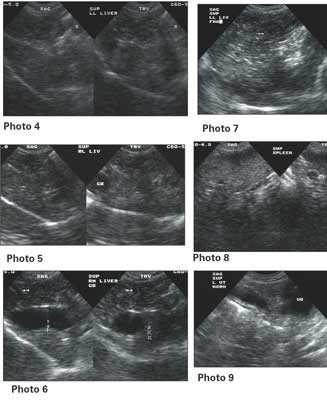

Signalment: Canine, Chinese Shar Pei, 3-year-old, female, 41 lbs.